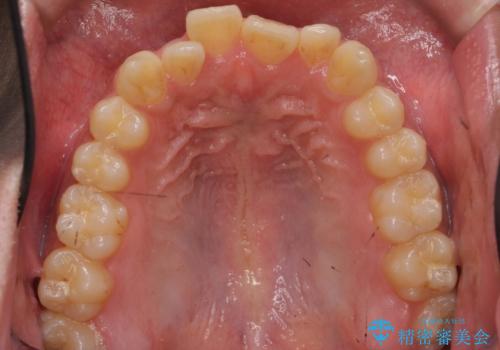

骨格性の受け口 非抜歯で下の歯を後ろに下げる インビザラインで インプラント矯正

- 受け口を主訴に来院。

当院では下の歯を後ろに下げるため矯正用ミニスクリューを用いてしっかり移動を行う等ご説明をし、治療開始しました。